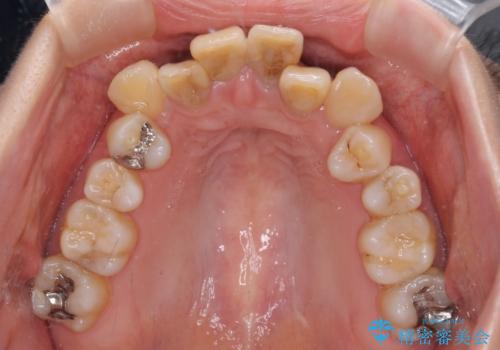

- 前歯の八重歯やデコボコを気にして来院された患者様です。

口元の突出感はありませんが、前歯の重なりが著しいため、目立ちにくい表側のワイヤー装置にて、上下左右の第一小臼歯4本を抜歯して矯正治療を行うこととしました。

上顎前歯4本は、以前むし歯により神経をすべて取り除かれており、その影響で既に変色を起こしている状態でした。

4本とも歯根部先端の骨が炎症により吸収していることがレントゲン写真から示唆されたため、矯正治療後に4本を再根管治療し、その後上顎6歯をオールセラミッククラウンにて補綴治療することとしました。